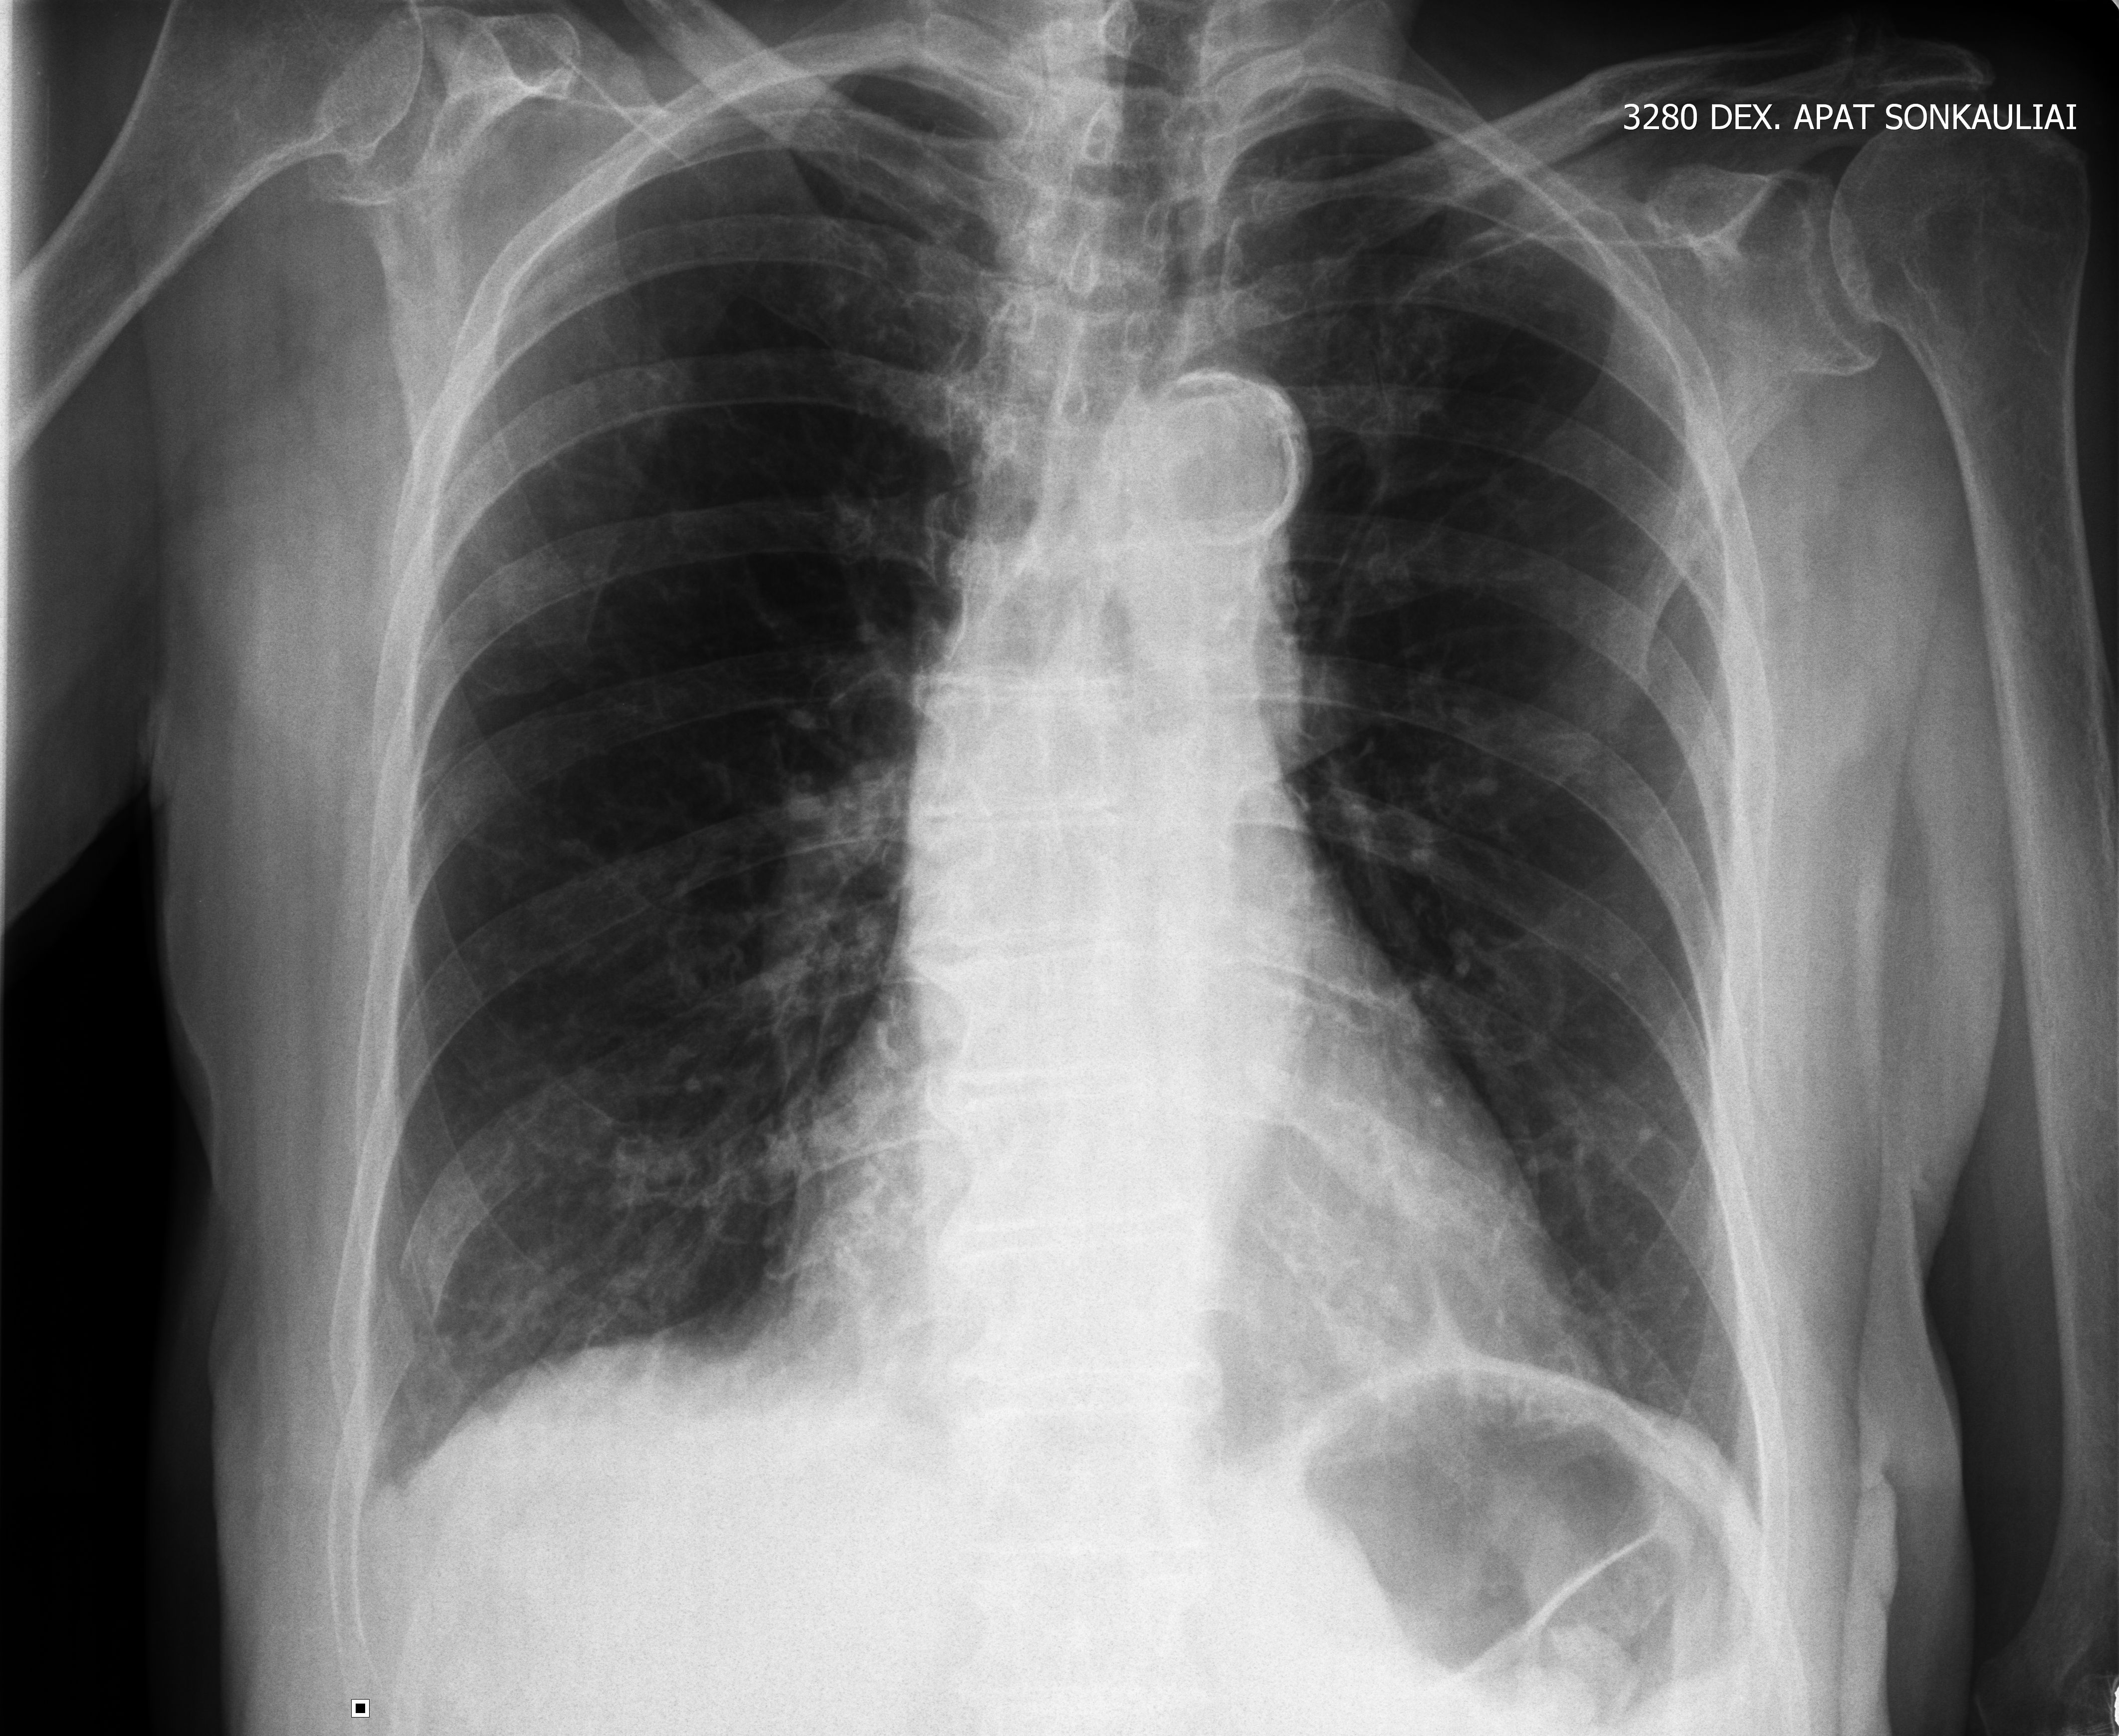

Пожилая женщина, ударилась об угол стола.

Рентгенологически описан только перелом X ребра справа.

При УЗИ имеются признаки перелома X и IX ребер (IX - оскольчатого), подкожной эмфиземы, пневмонии и плеврита.